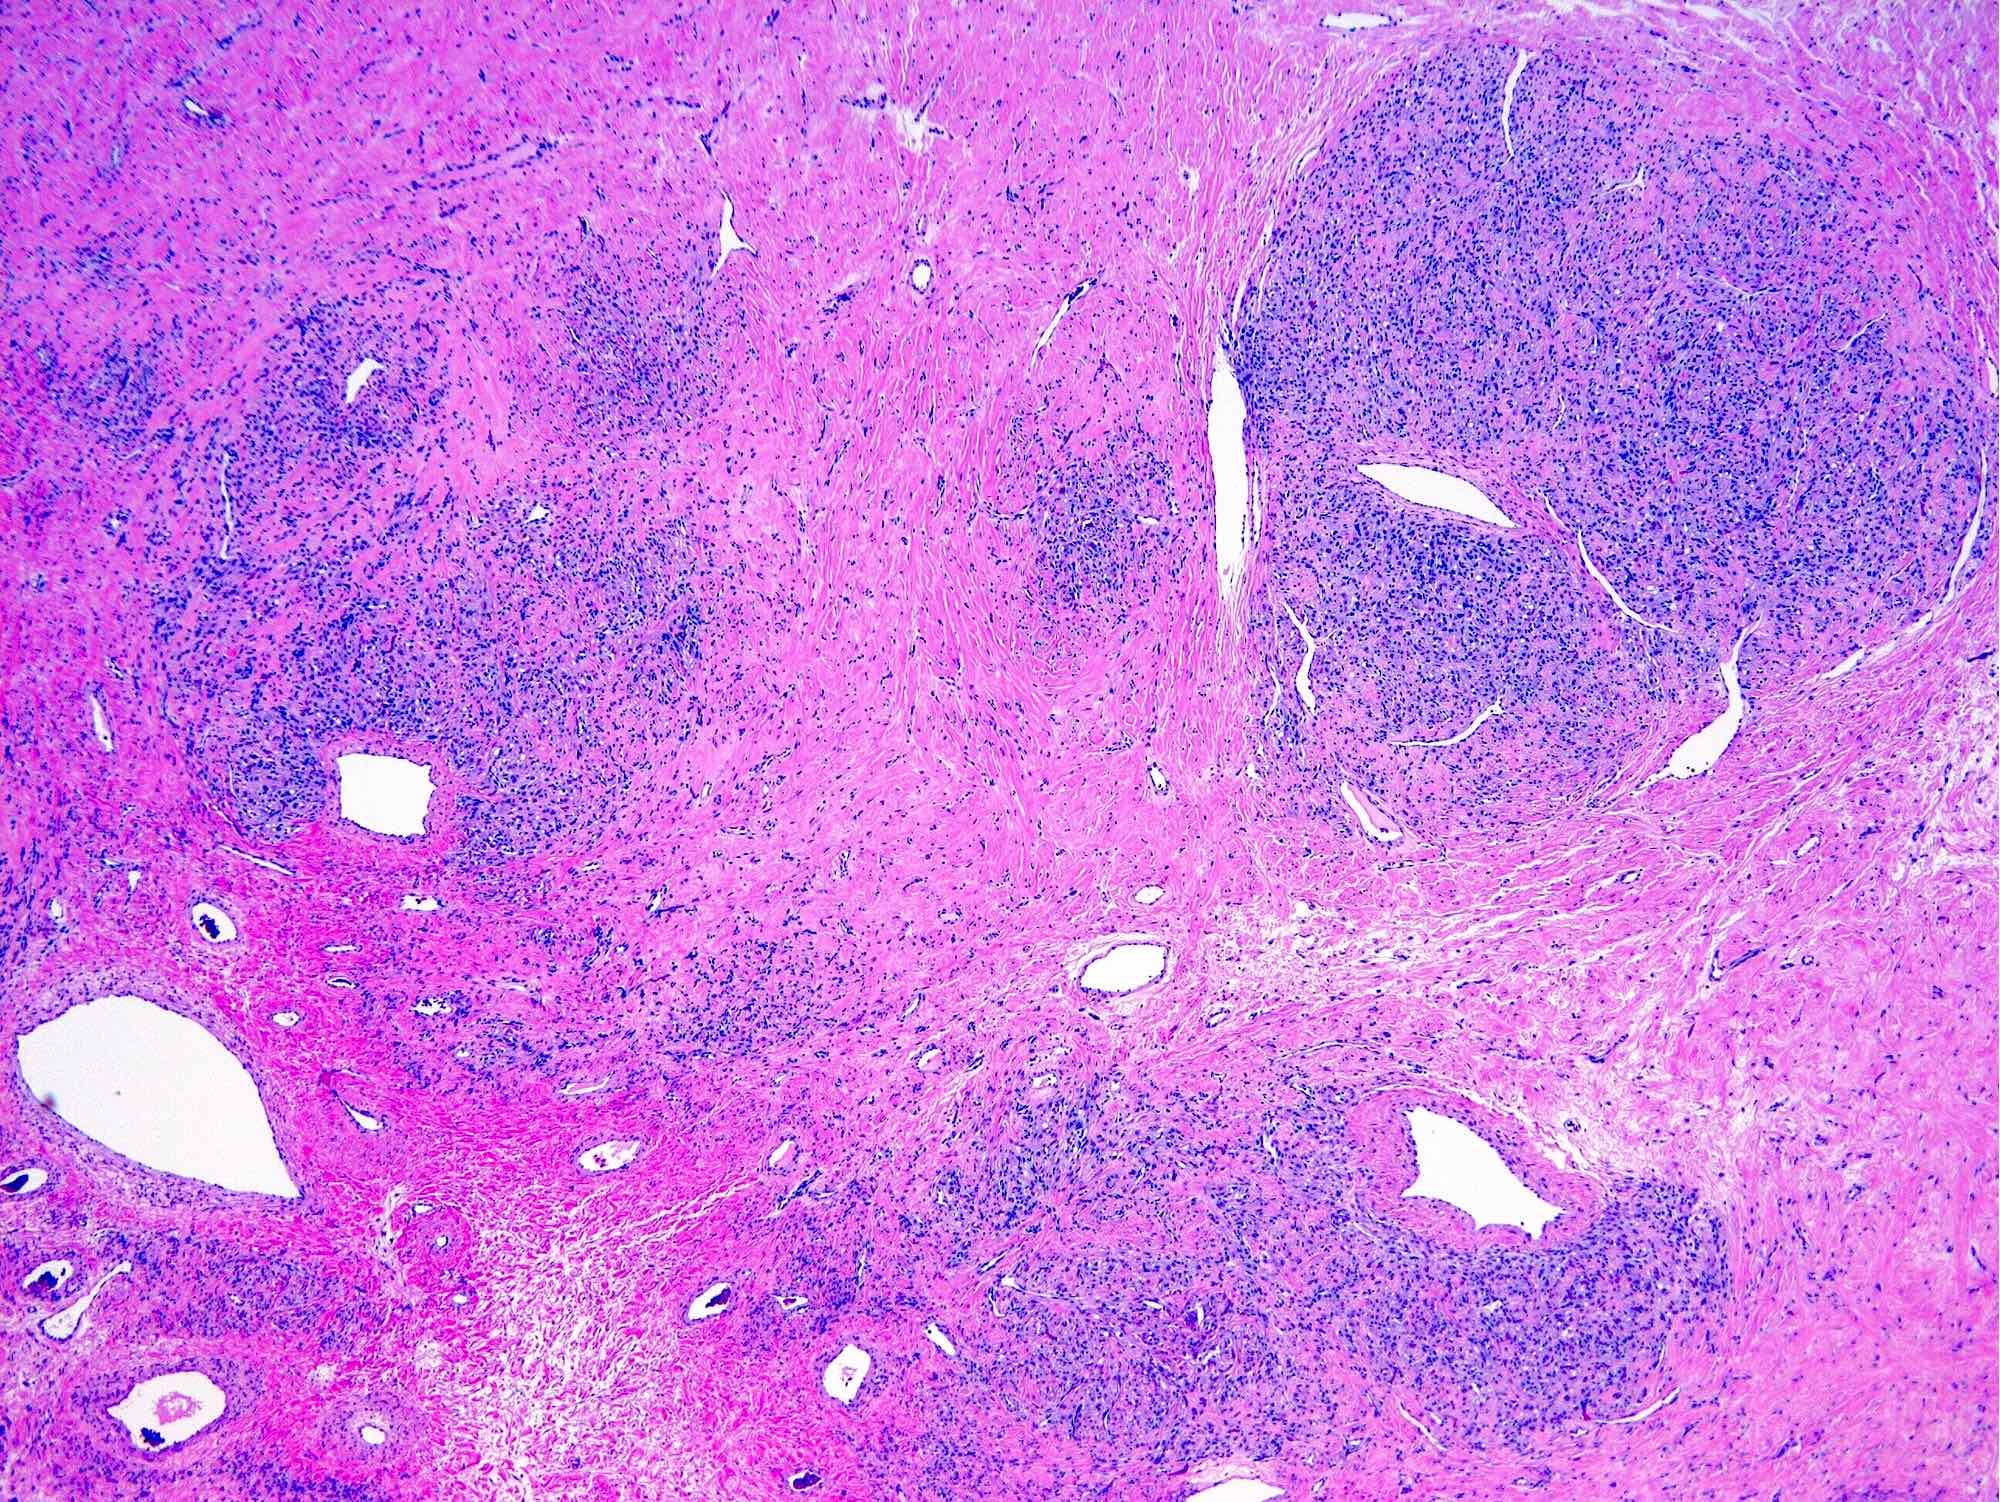

Microscopic (histologic) description

- Alternating cellular and hypocellular areas impart a pseudolobular appearance

- Hypocellular foci may be ill defined in pregnancy due to expansion of the pseudolobules by lutein cells (Int J Gynecol Pathol 2015;34:357)

- Thin, dilated and branching hemangiopericytoma-like vasculature is often conspicuous in both components

- Pseudolobules comprised of a jumbled admixture of epithelioid (lutein) and spindled cells with minimal atypia

- Hypocellular areas can be edematous, collagenous (variably keloid-like) or myxoid

- References: Cancer 1973;31:664, Histopathology 2022;80:360

Microscopic (histologic) images